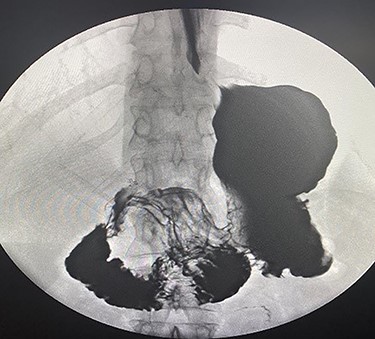

A 35-years-old female, 9 months post-endoscopic gastroplasty presented to the emergency department complaining of epigastric abdominal pain for 5 days, the pain is radiating to the umbilicus associated with nausea and vomiting. On general examination, she is vitally stable with HR 88 B/min, BP 116/66 and temperature 36.9°C, the abdominal examination showed epigastric and tenderness. On abdomen CAT scan, she had partial small bowel obstruction with adhesive band originating from the stomach (Fig. 1). Barium meal showed dilatation of the second part of duodenum due to band like structure (Fig. 2). The patient admitted to the hospital with a diagnosis of small bowel obstruction and kept NPO; Nil Per Os, on IV fluids and nasogastric tube drainage.

CAT scan showing partial small bowel obstruction with adhesive band originating from the stomach.